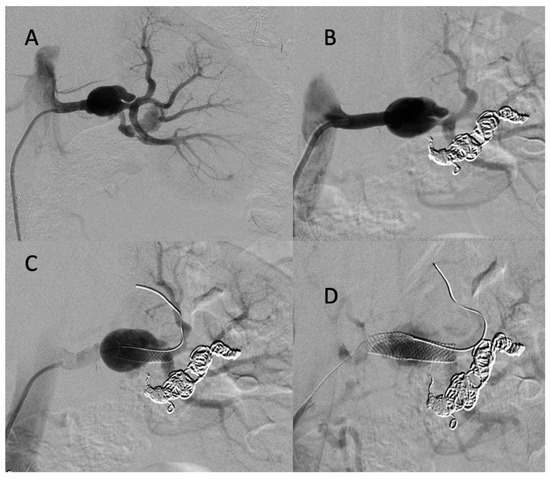

A 43-year-old female patient with a clinical and genetic diagnosis of vEDS (Gly mutation) visited our emergency room in a state of hemorrhagic shock. An enhanced abdominal CT scan showed a retroperitoneal hematoma surrounding the right kidney, with a ruptured aneurysm of the right renal artery. The patient was referred to the interventional radiologist. Under local anesthesia, the right renal artery was reached using a 6 F RDC catheter (Cordis-Santa Clara, CA, USA), and the right renal artery was then embolized using multiple IDCs and interlocking coils (Figure 7) without any complications during the procedure.

Figure 7.

(A) Digitally subtracted image from the right renal artery revealing the distal aneurysm with irregular walls (arrow). (B,C) Postembolization by coils.

CT scan follow-up demonstrated an increase in the dissection of the left renal artery aneurysm, and multidisciplinary teams decided to refer the patient to interventional radiology for the embolization of the left retropyelic artery and prepyelic artery stenting. Under local anesthesia, a 6 F introducer was inserted into the left femoral artery, and the left renal artery was reached using a 5 F cobra catheter (COOK-MEDICAL). The left retropyelic artery was embolized with coils and a small amount of ethylene vinyl alcohol copolymer (Onyx, ev3, USA). Then, a two carotid wall stent (Boston Scientific, Marlborough, MA, USA) was deployed, 5 mm × 30 mm and 7 mm × 30 mm, in the prepyelic artery without any complications from the procedure (Figure 9).

Figure 9.

(A) Digitally subtracted image from the left renal artery dissection with aneurysm formation; (B) postembolization of the left retropyelic artery by multiple coils and a small amount of ethylene vinyl alcohol copolymer; (C,D) post-deployment of a two carotid wall stent in the left prepyelic artery.